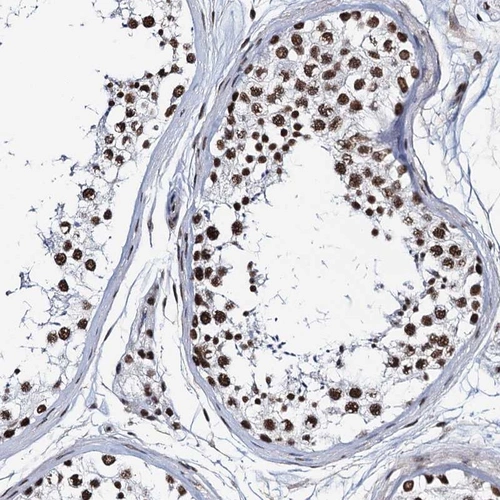

Immunohistochemical staining of human testis shows nuclear positivity in cells in seminiferous ducts.